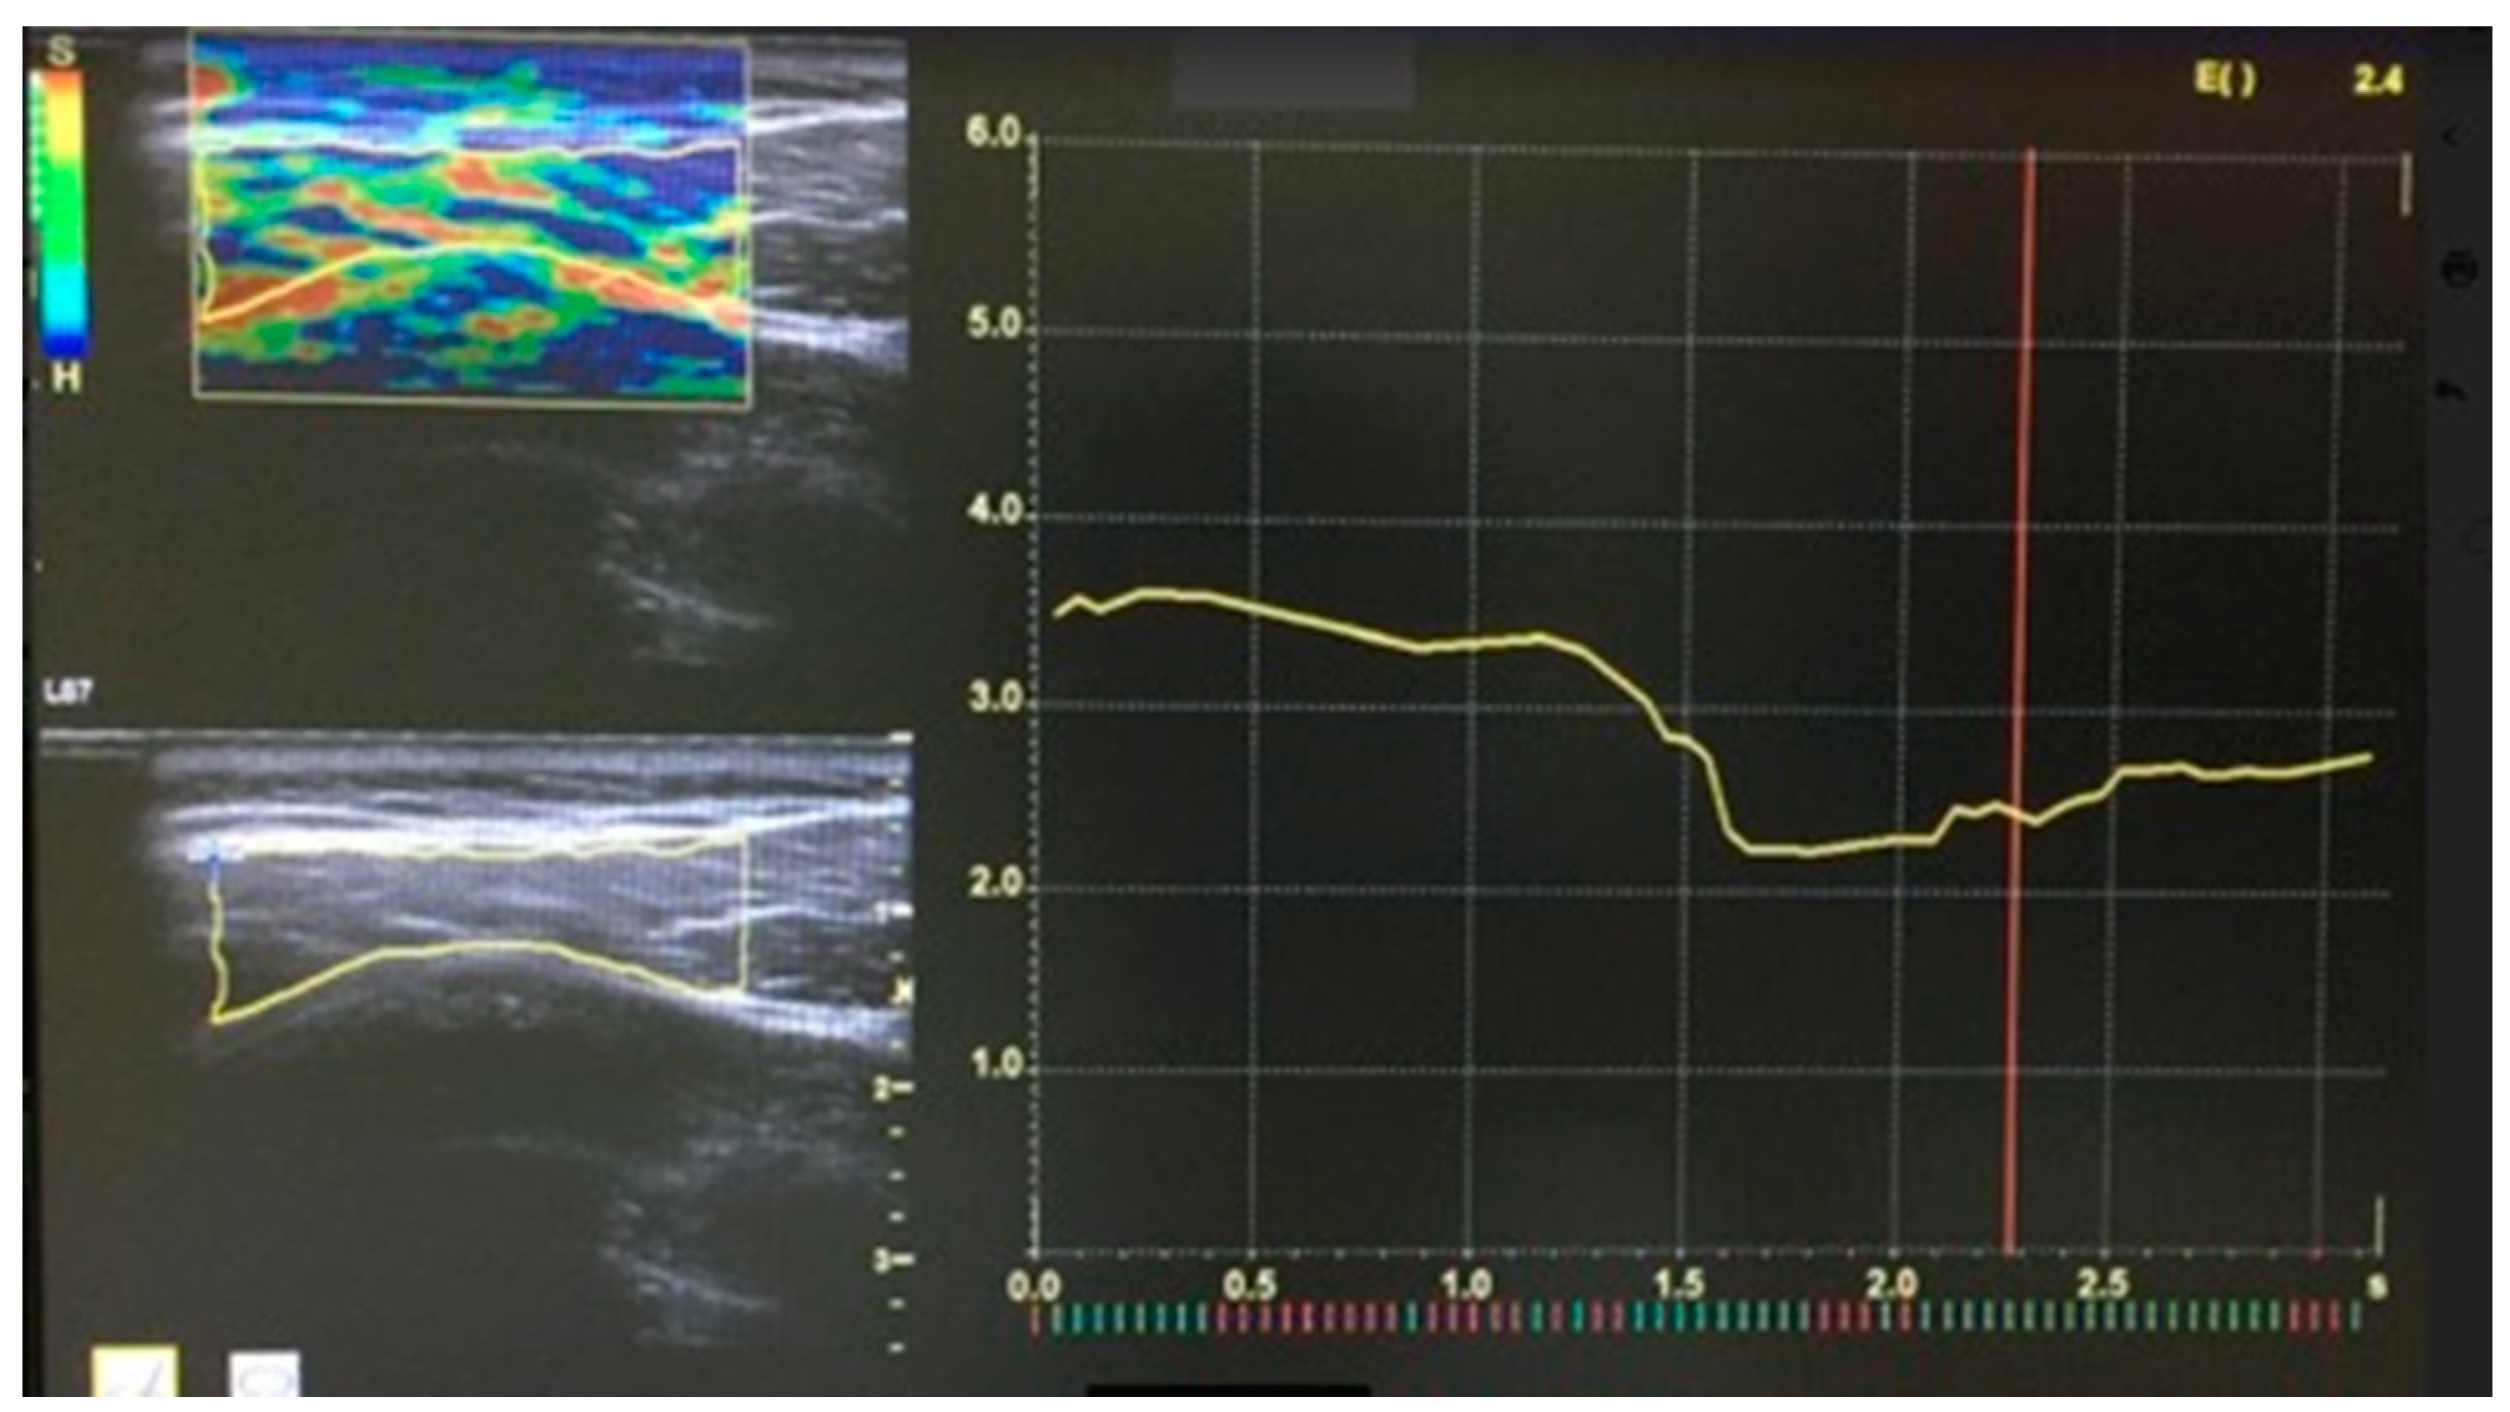

| EI | 2.14 ± 0.23 | 2.19 ± 0.21 | 0.571 |

| EI (T1) | 2.14 ± 0.23 | 1.84–2.21 | 2.19 ± 0.21 | 2.08–2.23 | 0.148 | 0.571 | 0.10–0.17 |

| EI (T2) | 1.35 ± 0.24 | 1.67–1.99 | 2.04 ± 0.23 | 1.92–2.17 | 0.628 | 0.003 * | 0.47–0.83 |

| EI (T3) | 1.18 ± 0.20 | 0.74–1.34 | 1.41 ± 0.26 | 1.26–1.55 | 0.371 | 0.034 * | 0.29–0.43 |

| EI (T4) | 0.93 ± 0.15 | 0.78–1.21 | 1.01 ± 0.13 | 0.96–1.15 | 0.131 | 0.856 | 0.09–1.14 |